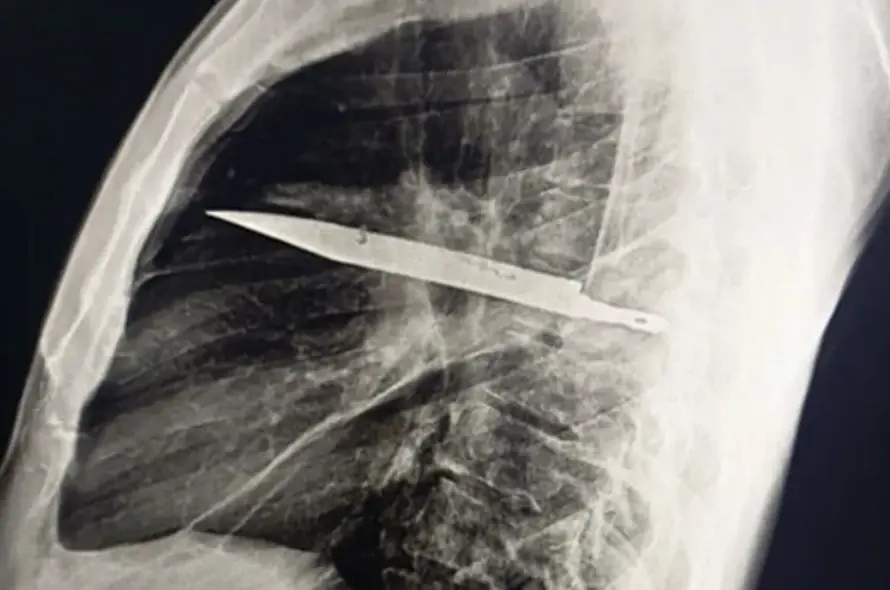

Doctors who examined him during this recent visit ordered an X-ray, which revealed a “retained metallic object” inside his chest. Further imaging confirmed the shocking finding: a knife blade had penetrated through his scapula (shoulder bone) and remained lodged deep within the chest cavity. Around the blade, a significant build-up of pus and necrotic tissue had formed, a sign that his body was beginning to respond to the foreign object after years of relative silence, according to PEOPLE.